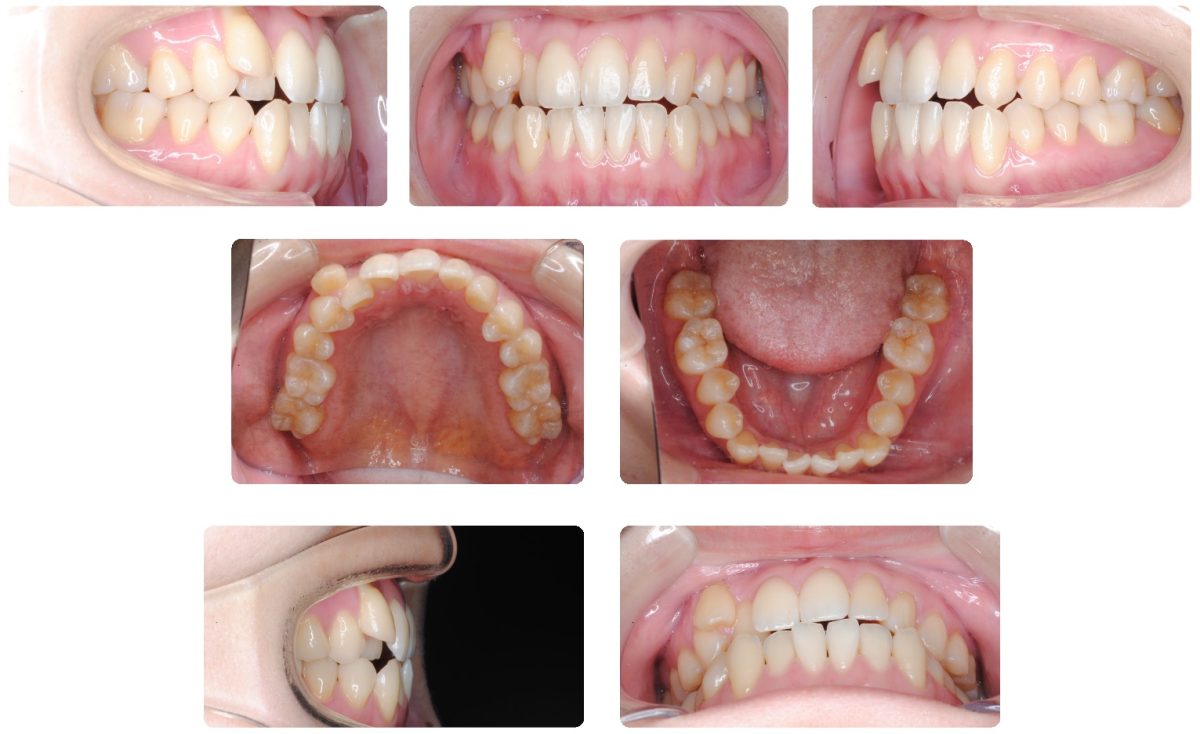

主訴:上下前歯正中のずれと八重歯、かみ合わせを治したい

初診時年齢:21歳

性別:女性

診断名:上顎低位唇側転位と側方編位の切端咬合

抜歯/非抜歯:非抜歯

上顎右側犬歯の位置と上下前歯正中のずれが気になるとのことで来院されました。上下前歯正中のずれが大きいことと上顎右側犬歯歯肉の退縮を考慮して小臼歯抜歯による治療も検討しましたが、舌が大きめであることからまずは小臼歯を非抜歯で治療を開始しました。